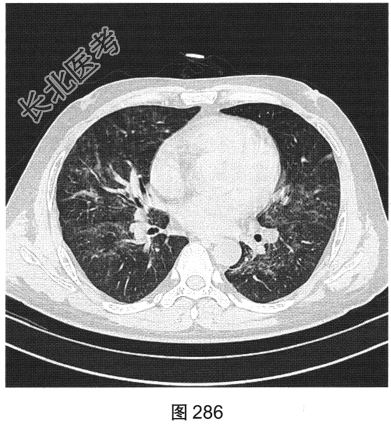

- [材料题] 患者男性,33岁,因“双下肢散在皮下出血点伴尿检异常3个月余,咳嗽、胸闷伴发热一周”就诊。患者脂肪肝、胆囊炎,服用莲葡双清片;随后几日内食用淡水鱼、鱿鱼、饮啤酒;5天后出现双下肢散在皮下出血点,未重视;10天后出现腹痛,在当地医院检查尿中有蛋白、定量不详,血常规检查正常,肾功能正常,应用醋酸泼尼松效果欠佳,行肾活检术,病理诊断:紫癜性肾炎,继发IgA肾病。患者每天静脉滴注甲泼尼龙0.5g,共3天,后改为口服甲泼尼龙28mg/d,共35天。一周前着凉后出现咳嗽、胸闷伴发热,体温达39.1℃,于当地医院抗炎治疗效果欠佳,遂来本院。实验室检查:血白细胞计数6.92×109/L,中性粒细胞0.845,CRP为2.7mg/dl。患者PP65阳性。胸部CT检查如图284~图287所示。

- 多项选择题2.根据患者病史和影像特征,您的诊断是( )

A、肺结核

B、巨细胞病毒感染

C、急性肺泡损害

D、外源性过敏性肺泡炎

E、肺水肿

F、肺孢子菌感染

- 多项选择题4.该病的常见影像表现有( )

A、空洞

B、双肺磨玻璃影

C、淋巴结增大

D、实变

E、小叶中央结节一树芽征

F、血管支气管束和小叶间隔增厚